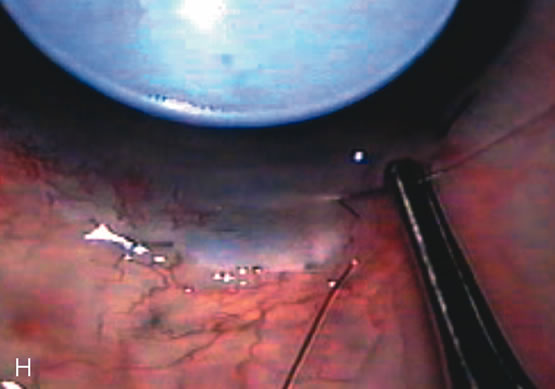

Fig. 8. Bleb appearance after limbus-based versus fornix-based conjunctival flaps. Even though the IOP is thought to be equivalent between limbus and fornix-based conjunctival flaps, the final bleb appearance varies considerably. A. During a limbus-based approach, an incision through conjunctiva 10 mm posterior to limbus will sever through multiple arterial vessels, increasing the likelihood of an avascular bleb. B. The tissues are dissected down to the sclera further cutting feeder vessels from Tenon's capsule. C. The wound is closed inciting a cascade of wound healing events that may ultimately lead to scarring producing a barrier to aqueous flow. D. This leads to walling off of a bleb that has lost some of its overlying vascularity (pale cystic avascular bleb). E. During a fornix-based conjunctival approach, the incision is made at the limbus and tissues undermined. F. The incision is closed at the limbus; no conjunctival vessels are severed over the bleb area. G. This fosters the formation of a shallow diffuse pale bleb with a normal vessel pattern.